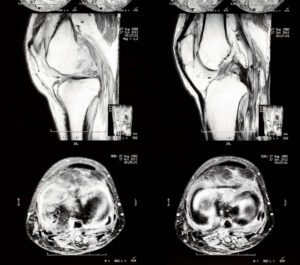

Knee arthrogram:

• Detects: Meniscal tears, ligament injuries (ACL, PCL, collaterals), cartilage lesions, post-surgical complications

• Less common (standard MRI often sufficient)

• Why it’s ordered: When standard MRI is inconclusive or post-surgical evaluation needed